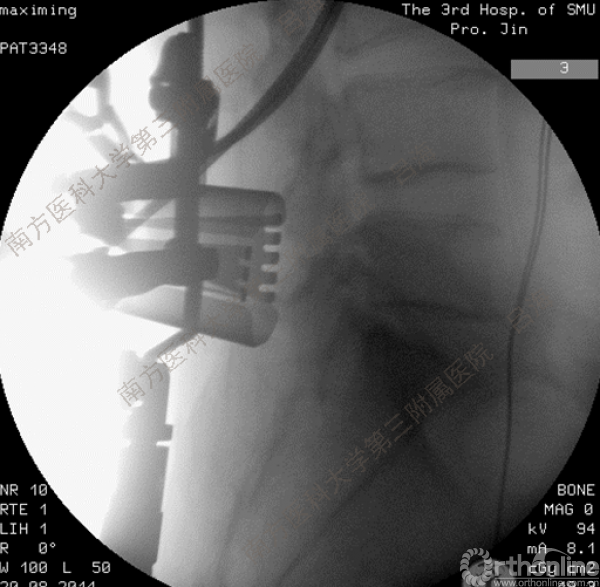

随着社会老龄化进程加快,胸腰椎退行性病变的治疗已经成为脊柱学术界的一个热点话题。MIS-TLIF手术可以治疗多种不同的胸腰椎退行性疾病,南方医科大学第三附属医院吕海教授结合病例为我们一一展示了该术式在治疗不同胸腰椎疾病时的具体手术过程。